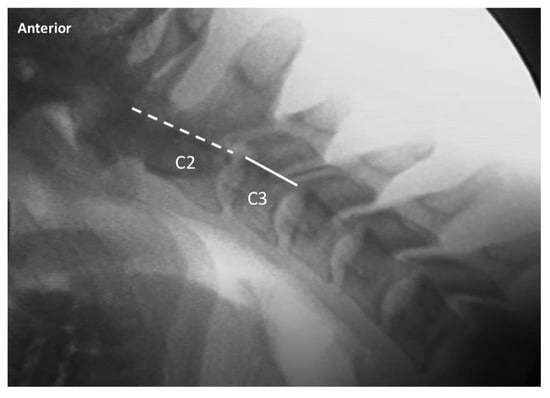

| Translation (lat) | C2-7 | Lateral flexion-extension | Maximum anterior (in flexion) or posterior (in extension) translation of vertebral body relative to adjacent inferior vertebra, measured at posterior vertebral body line | 2 mm or less anterior or posterior translation |

| C2-7 translation (lat view) | 0–2 mm | 0–2 mm > 2 mm |

| > 2–3 mm | ||

| > 3–4 mm | ||

| > 4 mm | ||